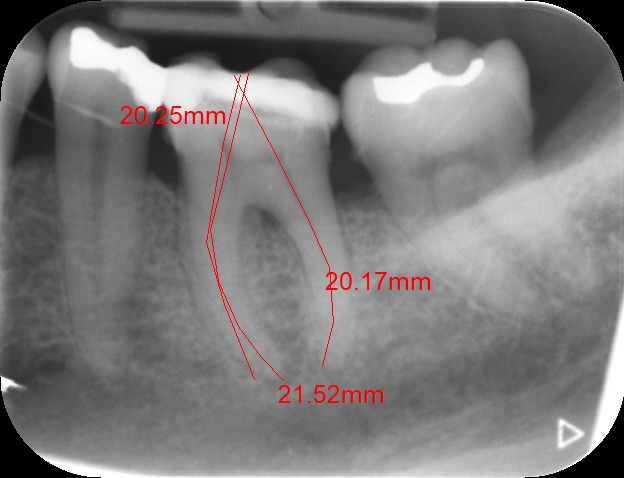

An access cavity is placed on the surface where the patient bites, to reach the root canals of the tooth. Once all the canals are identified, small files are used to remove the infected pulp.

Files of different sizes are used to eliminate bacteria and infection and to shape the canals. The canals are disinfected thoroughly with irrigants and later the canals will be sealed in 3 dimensions with a special medicament called gutta-percha to prevent reinfection of the tooth and the access cavity will be sealed with a temporary filling.